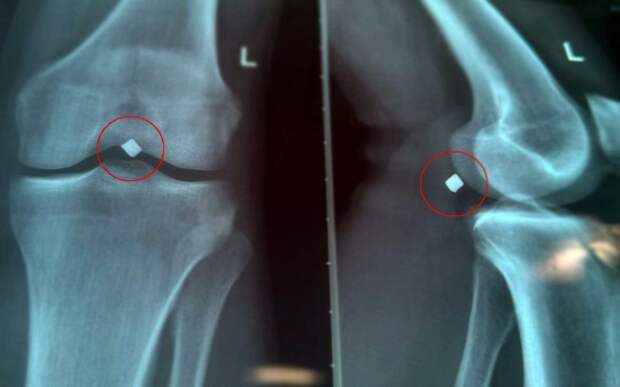

В июне 2025 года молодой человек получил ранение осколком. Инородный предмет пробил в теле надколенник, прошёл через коленный сустав и застрял в паре миллиметров от пучка нижней конечности. Пациент мучился от постоянных болей, каждый шаг отдавал мучением.

Во время операции по извлечению осколка выяснилось, что инородное тело лежало прямо на стенке подколенной вены, это создавало прямую угрозу кровотечения.